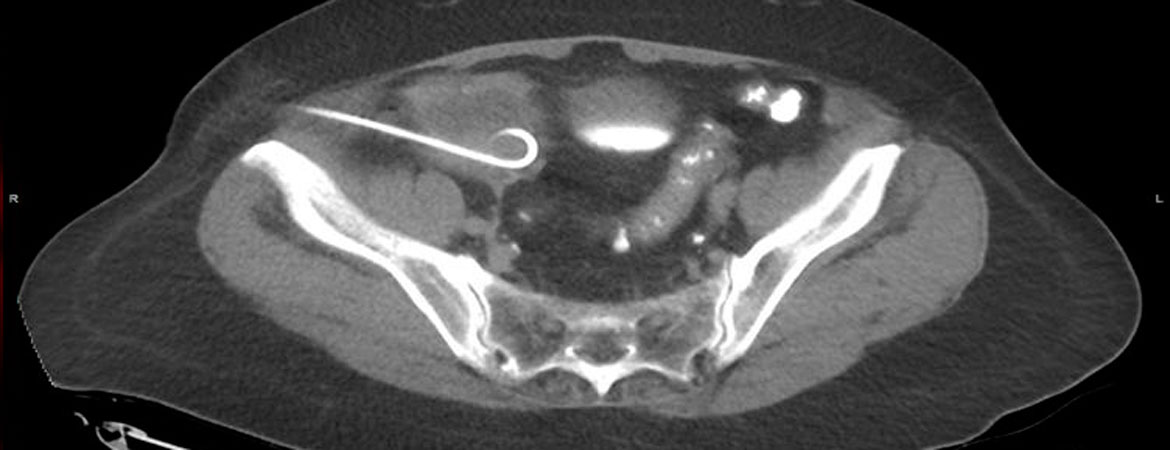

Almir Miftaroski, Ulf Kessler, Etienne Monnard, Bernhard Egger (Author) Two-step procedure for complicated appendicitis with perityphlitic abscess formation Fulltext PDF Fulltext HTML